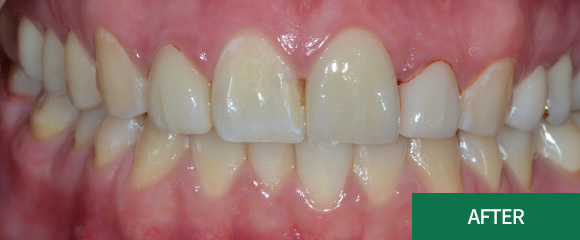

심미치료

심미레진

전체미백

실활치미백